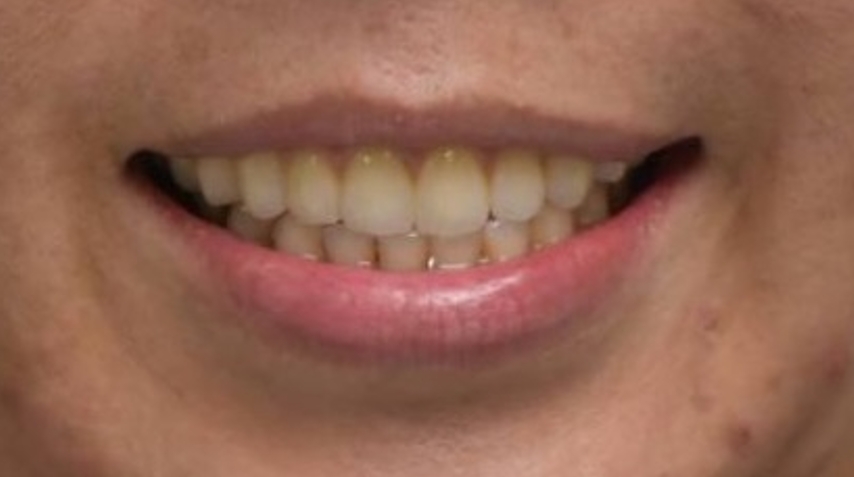

團隊也模擬了因上顎骨大量缺損,將植體植入顴骨中;手術當天,團隊結合了術前規劃的3D列印切割導引板與即時電腦導航系統,在一次性的手術中,精準完成上顎口腔癌腫瘤切除、頸部淋巴廓清、取用自體組織的游離皮瓣重建,以及高難度的顴骨植牙等四大關鍵程序。

中山附醫也強調,這種「一站式」的整合手術,將過去可能需要分次進行、耗時數月的療程,濃縮在一天內完成,大幅縮短了治療時間,也顯著降低了患者的身體負擔與麻醉風險。